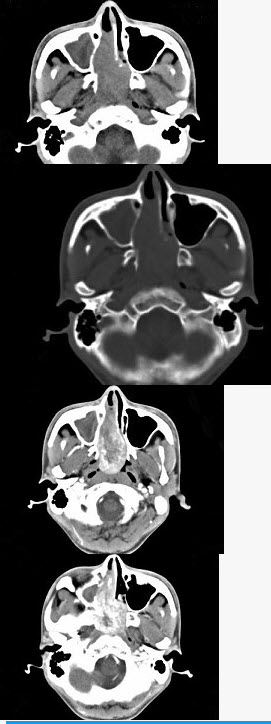

- 单项选择题男,20岁,头痛、鼻塞、鼻出血,CT如图所示,最可能诊断为()。

- C